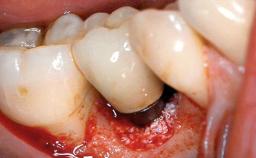

A 77-year-old male patient was referred for the management of frequent and repeated acrylic fracture of his existing mandibular fixed full-arch implant-supported metal/acrylic prosthesis. He also complained about softtissue soreness and the lack of retention and stability of his maxillary removable partial metal/acrylic prosthesis. Both prostheses had been delivered two years previously as part of his full-mouth rehabilitation (caries, tooth wear, tooth fracture). His medical history revealed high blood pressure, controlled with the use of antihypertensive medication.

Defining Characteristics Fully edentulous lower jaw to be rehabilitated with an implant-borne fixed dental prosthesis

Retention Screw-retained, with 4 or more splinted implants Screw-retained, with 4 or more splinted implants